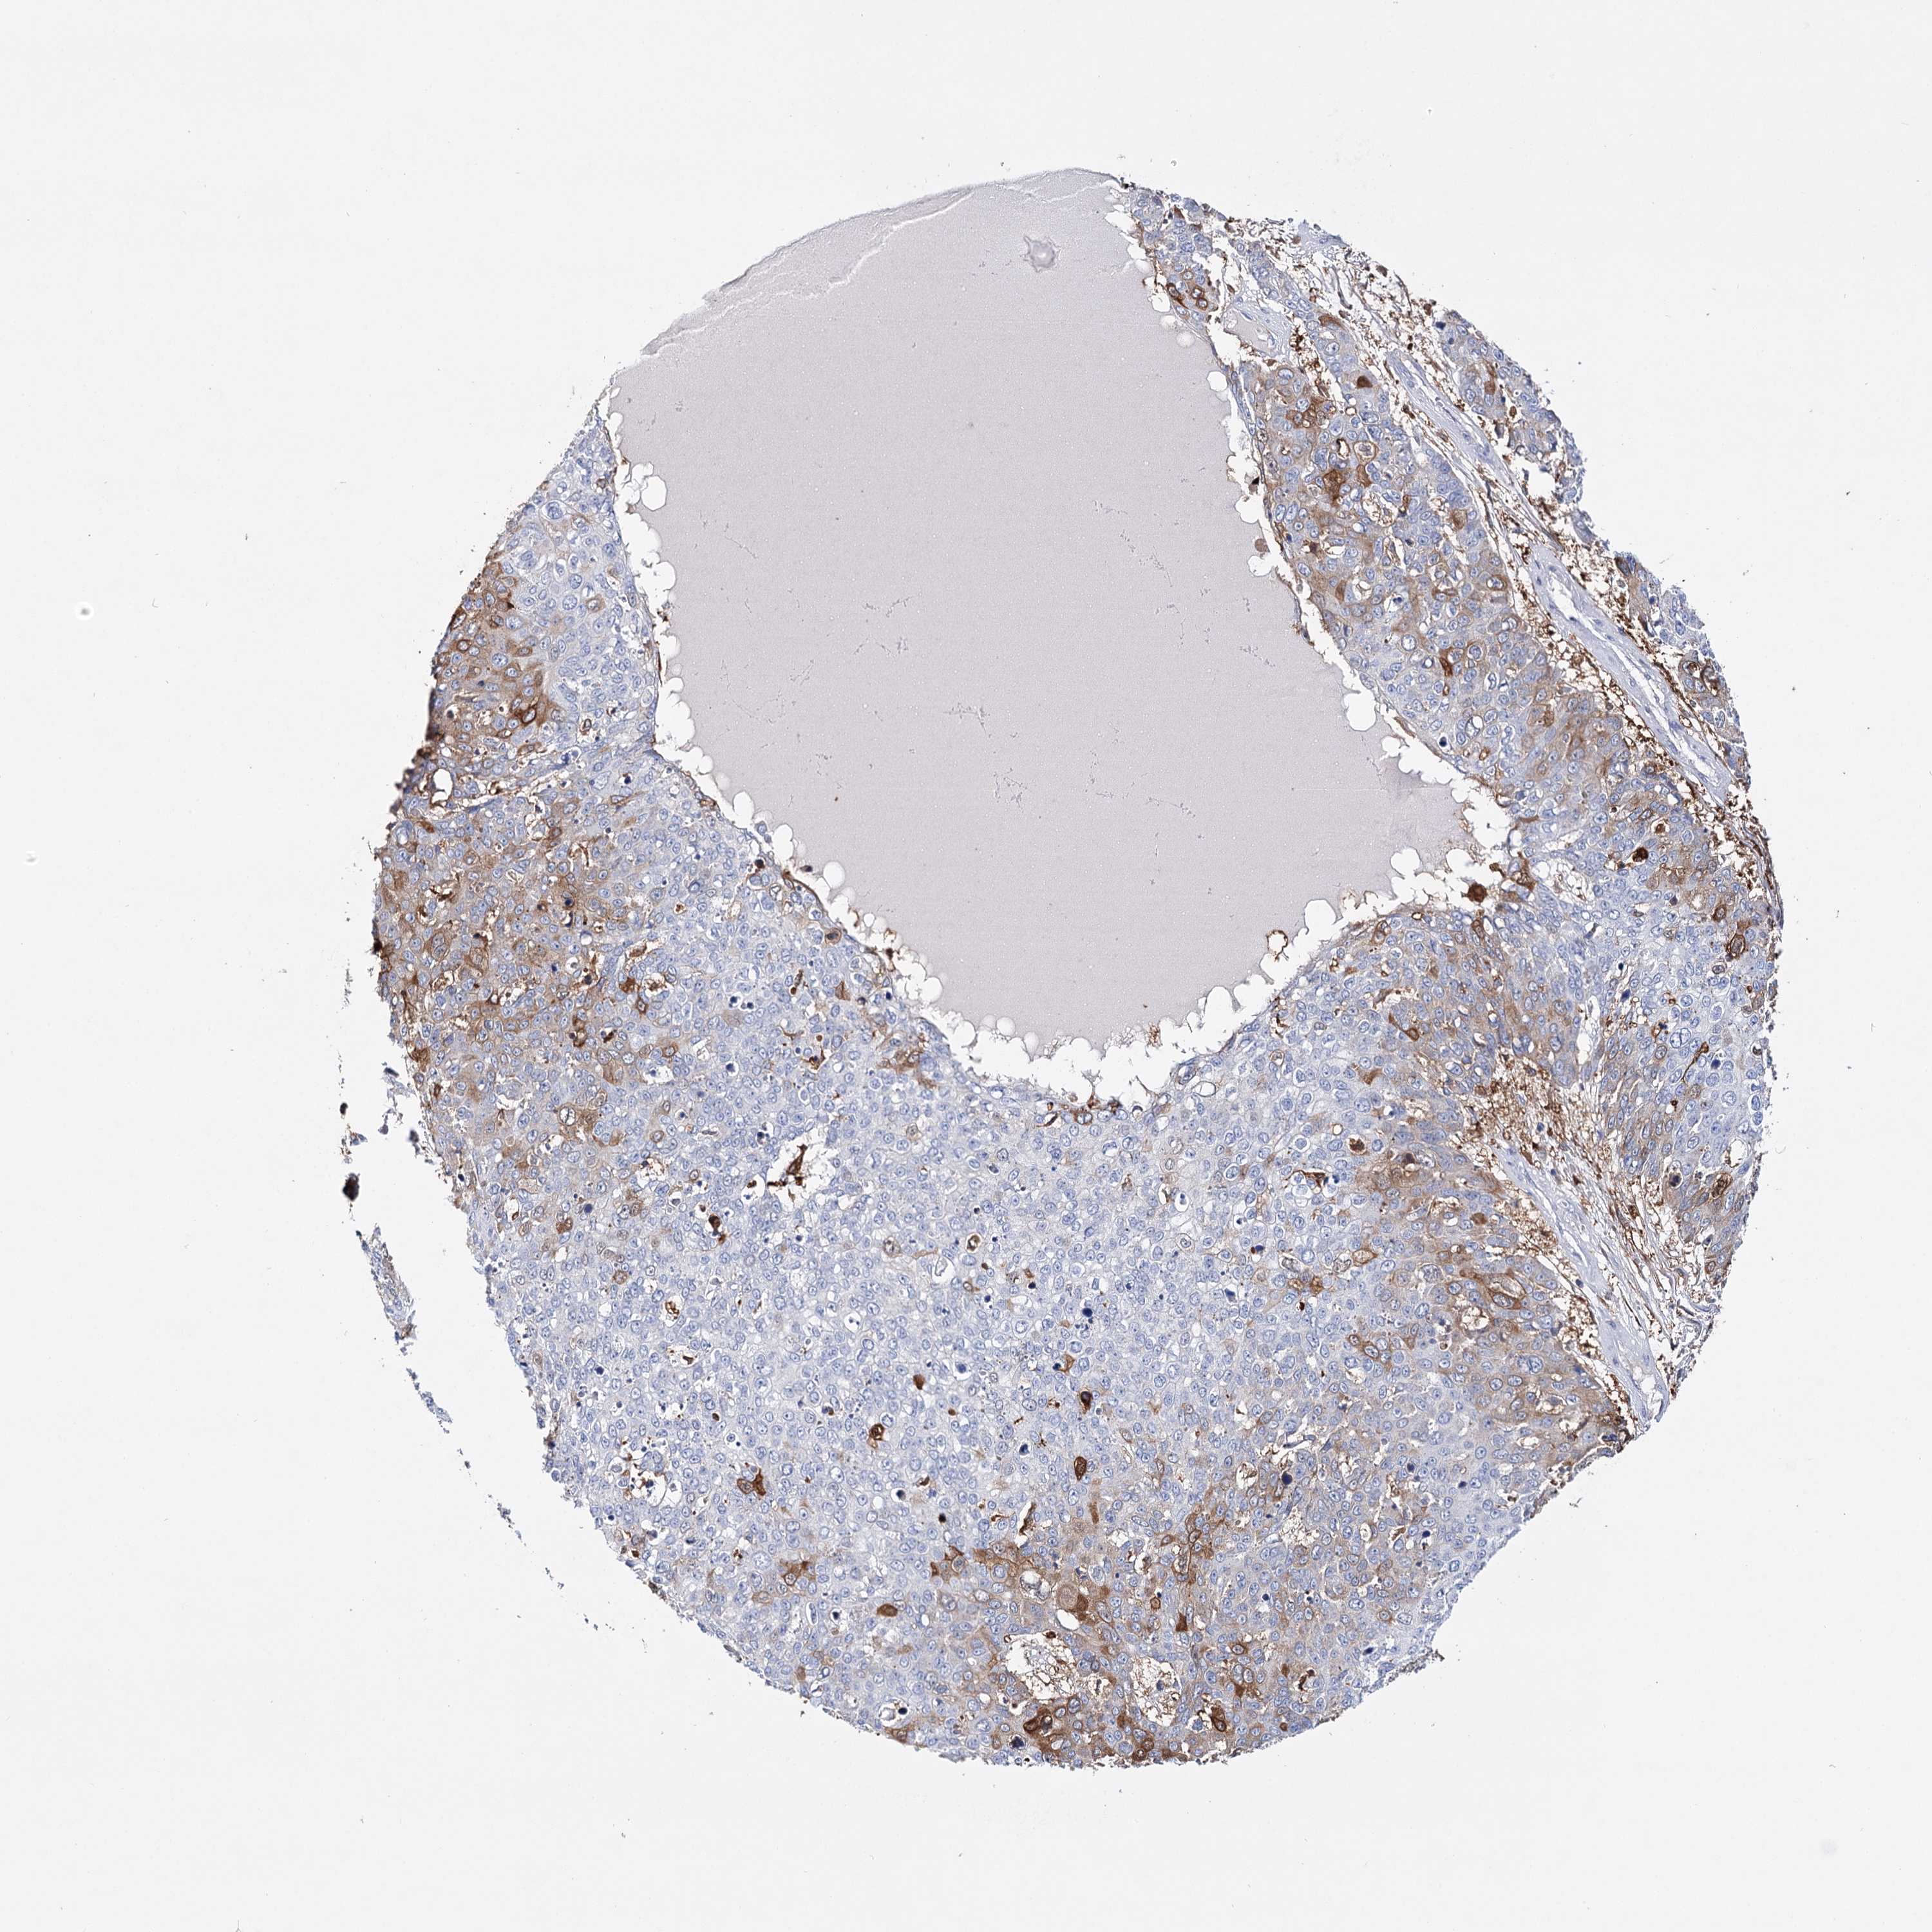

SKIN CANCER - Protein expressioni

A mouse-over function shows sample information and annotation data. Click on an image to view it in a full screen mode. Samples can be filtered based on level of antibody staining by selecting one or several of the following categories: high, medium, low and not detected. The assay and annotation is described here.

Each image is clickable and will lead to virtual microscopy that enables deeper exploration of all samples and also displays staining intensity scores, fraction scores and subcellular localization as well as patient and tissue information for each sample.

Antibody HPA038034

Squamous cell carcinoma, NOS